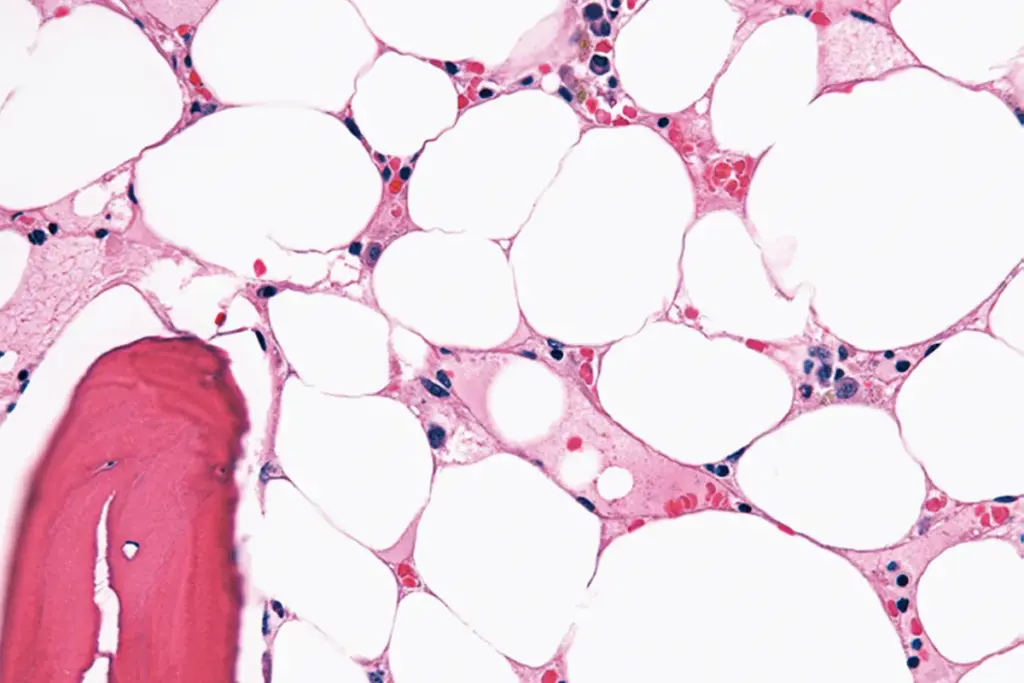

Bone Marrow Biopsy Procedure

A bone marrow biopsy is a key test for diagnosing bone marrow failure. We take a sample from the hipbone. This lets us see how the bone marrow is working and if there are any problems.

- Bone Marrow Biopsy: This test looks at bone marrow tissue to check its cell count and find any problems.

Bone Marrow Cellularity |

Typically hypocellular |